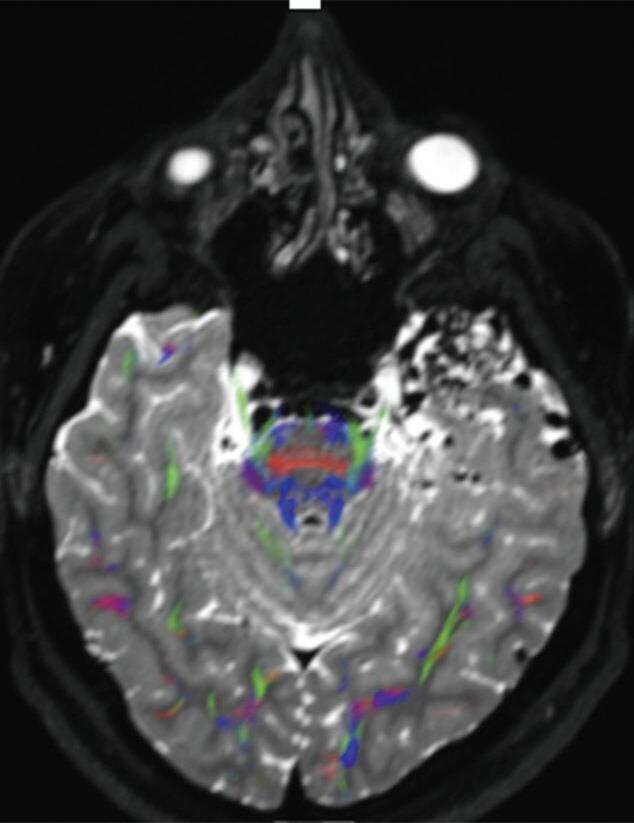

Fig. 1-9. RNM T2 em cortes (a) axial e (b) sagital. (c,d) Tractografia axial – sagital, demonstrando a posição de uma MAV não rota localizada na superfície basal do lobo frontal, nos giros orbitários e reto à direita (setas longas). Arteriografia digital cerebral com injeção de contraste via carótida direita, (e) AP e (f) em perfil demonstrando MAV nutrida por ramos da artéria cerebral média e cerebral anterior direita e drenagem para o seio sagital superior (seta curta).

A utilização de técnicas avançadas, como a tractografia (Fig. 1-23), reconstruções 3D, permitem um estudo detalhado de estruturas anatômicas e sua relação com as patologias cerebrais, facilitando assim o planejamento cirúrgico. A tractografia, uma técnica de ressonância magnética, permite estudar os tratos da substância branca do cérebro, mostrando sua posição, anatomia e integridade, por meio da análise do movimento das moléculas de água no tecido cerebral.35

tractografia cerebral, cortes axiais. A codificação de cores demonstra as fibras com orientação laterolateral em vermelho, a orientação anteroposterior em verde e a craniocaudal em azul. Observe o deslocamento das fibras de associação (verde) no lobo temporal esquerdo em relação à MAV.